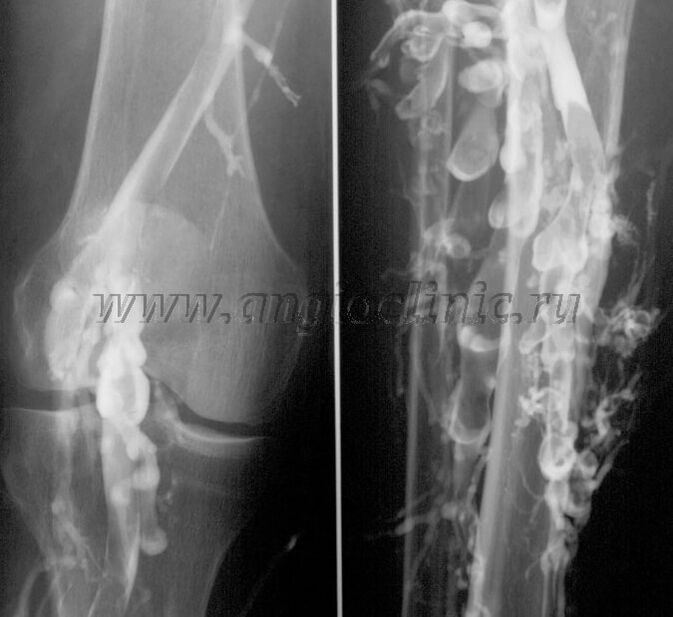

Contrast venography

Usually, ultrasound is sufficient for a complete diagnosis of venous pathology, but in some cases it is necessary to study the relationship between the state of the deep and superficial venous system, especially in case of relapses of varicose veins and secondary varicose veins.

To resolve these problems, radiographic examination with contrast is used.The saphenous veins are punctured and contrast is administered.The movement of the contrast is observed on the monitor of the X-ray machine and all necessary tests and projections are performed.Currently, venography for varicose veins is used very rarely.